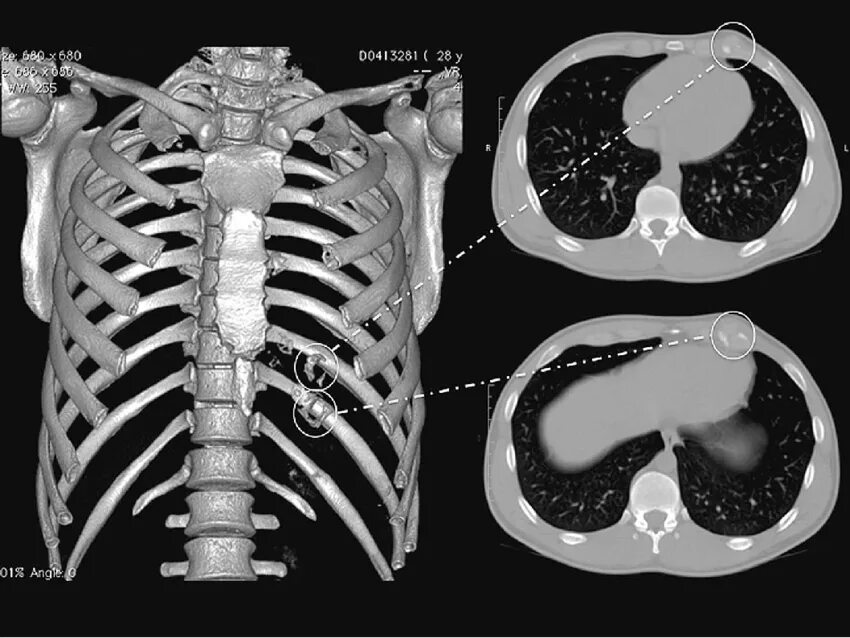

Множественные ребра